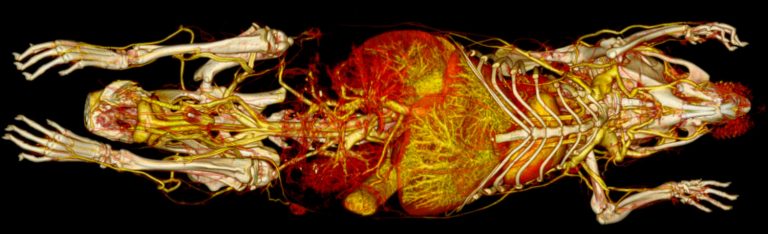

Milabs CT is capable of fast scanning and ultra-high-resolution scanning under low-dose X-rays, and the highest resolution can reach 10um.

- Contrast vascular imaging 3D simulation